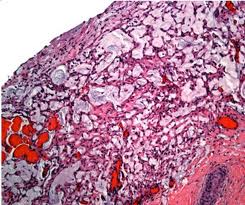

8. Angiosarcoma

These rare breast cancer tumors are also known as hemoangiosarcoma. Angiosarcoma has cells that produce fiber and cells that line the cavities.